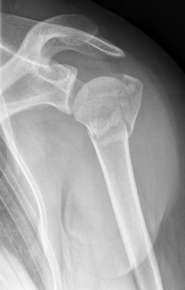

Proximaler Oberarmbruch5Proximaler Oberarmbruch6

Picture: Here is a subcapital upper arm break in a young woman. An angle stable plate osteosynthesis was performed to stabilize the head in correct position to the humeral shaft and shoulder joint. Especially in young patients, We strive to treat non-invasively and as gently as possible. This possibility is often due to the bone quality in young as opposed to older people.